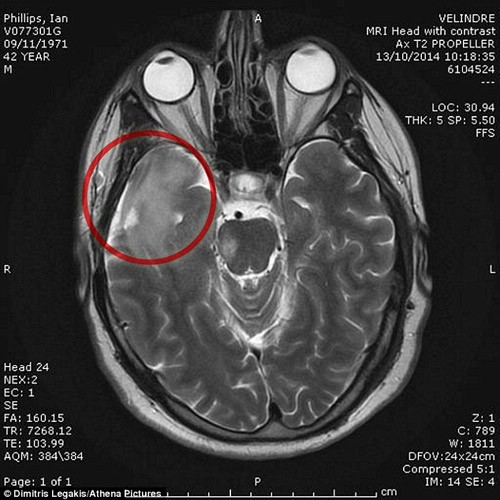

Các bác sĩ đã tìm thấy khối u có kích thước như quả chanh trong đầu Ian.